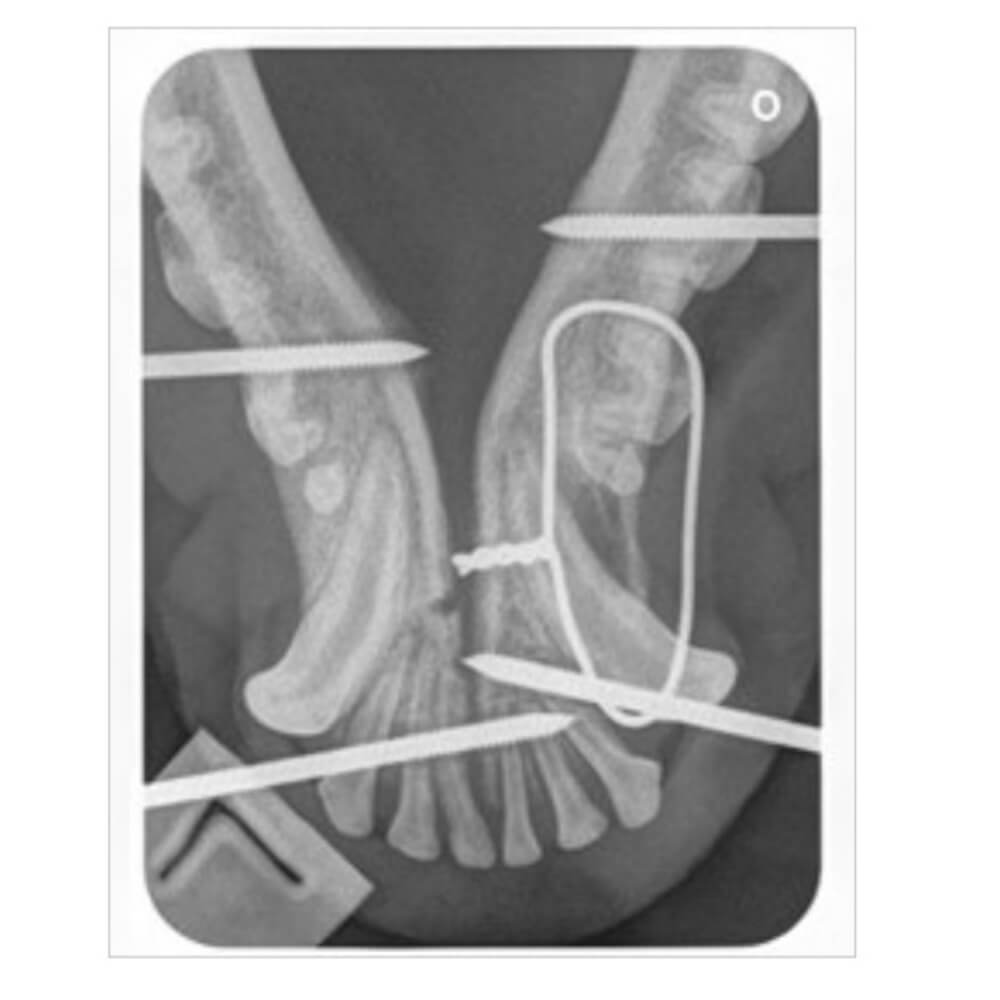

Under sedation radiographs were taken. Maya had fractured her jaw in two places which would require orthopaedic surgery to stabilise. Fortunately her lameness was only bruising and no other injuries were found.

Surgery stabilised the fracture with a combination of a bilateral external skeletal fixator and also an encircling wire. Maya went home with ‘bumpers’ on for two months to allow the bones to heal. The implants were removed at a second surgery. Maya has since made a full recovery, is always happy to see us, and continues to be her normal bouncy self!